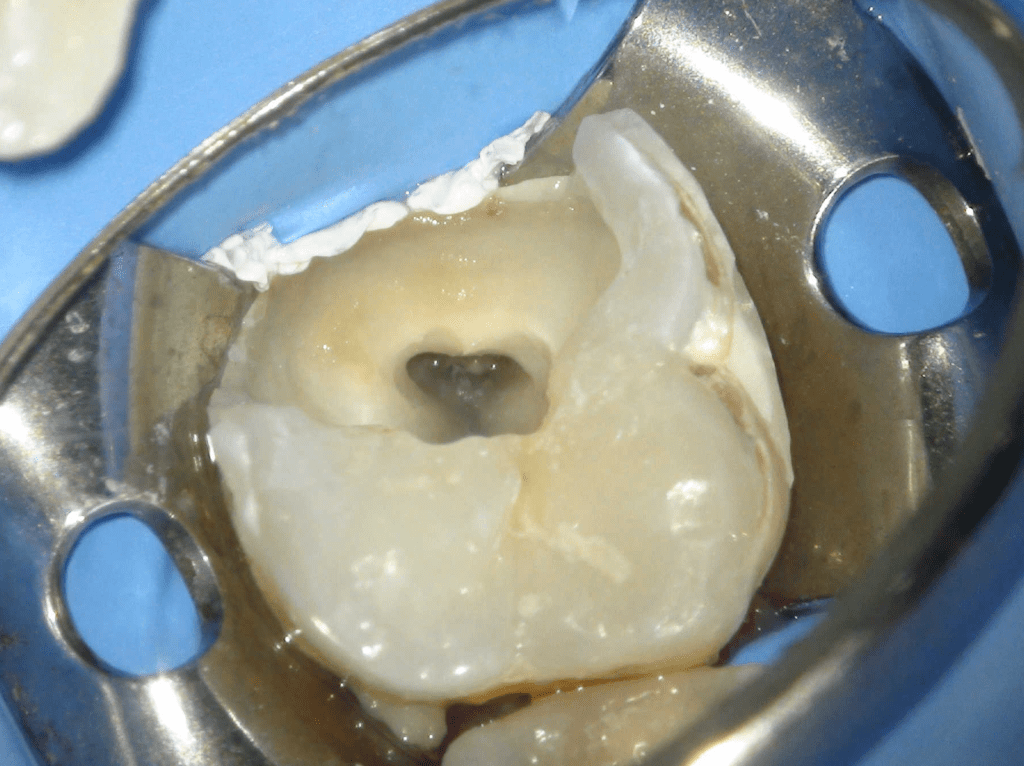

Pulpotomía biodentine + reco preendio